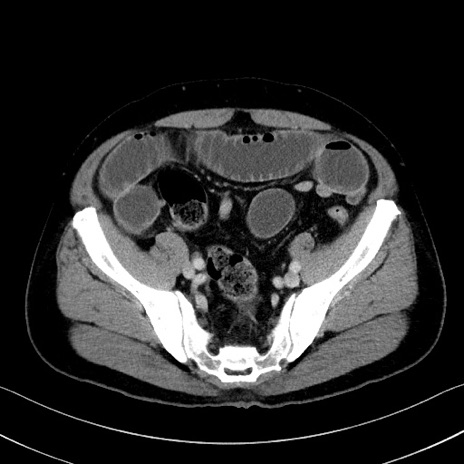

症例35(横断像)

【症例】70歳代 男性

【主訴】腹部膨満、嘔吐

【現病歴】昨日より腹部膨満感出現。本日増悪し、仙痛出現。嘔吐あり、受診。

【既往歴】糖尿病、胆摘後

【身体所見】BP 149/80mmHg、HR 74/min、BT 35.9℃、腹部:膨満、軟、圧痛なし。腸雑音減弱あり。上腹部正中切開瘢痕あり。

【データ】WBC 13500、CRP 1.72